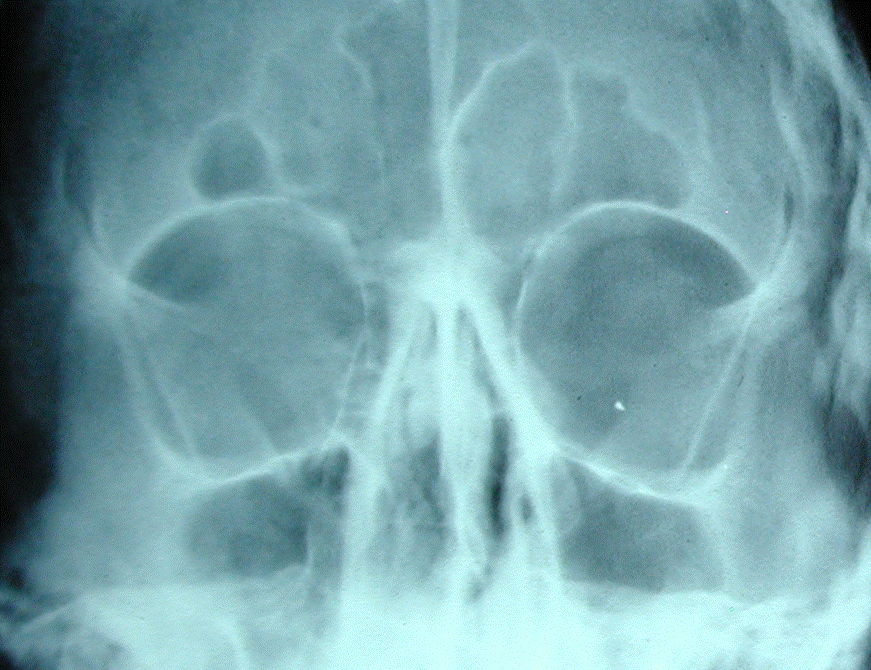

- Figure 10. Orbital X-ray showing intra-ocular FB